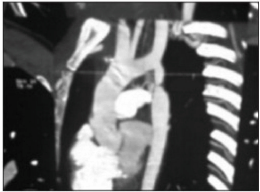

A coarctação da aorta é uma malformação cardiovascular congênita de elevada prevalência. É caracterizada por um estreitamento, sendo mais frequente no sexo masculino na razão de 2 a 3:1. A partir da imagem apresentada abaixo, assinale em qual porção da aorta há a coarctação: